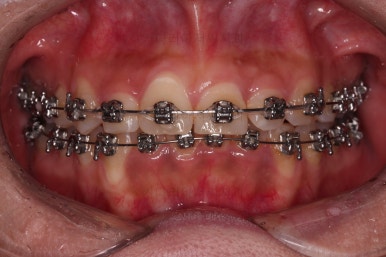

장치 부착 이후의 느낌도 봐주시고요.

치열이 점점 가지런해지죠?

조금만 더 하면 마무리를 할 수 있겠네요.

이번 환자분처럼 부산안면비대칭 있으신 분들은 미묘하게 양쪽 어금니의 각도라던지 앞니의 기울기 등 약간의 비대칭 느낌을 남겨놔야 치료가 종료 돼요.

위아랫니의 중앙선도 100% 맞추는 건 힘들고요.

적당한 선에서 기능이 잘되게 끔만 하고 마무리를 하게 된답니다.